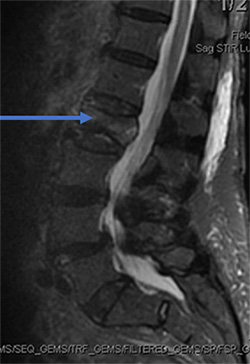

Clinical Example 1

88 year old female fell in the bathroom with increasing amount of back pain. Despite pain pills in the hospital, she could not get out of bed. MRI showed compression fracture due to osteoporosis (weak bone). MRI can show if the fracture is new based on swelling in the bone. The arrow shows the bone is whiter than the other bones indicating a new fracture.